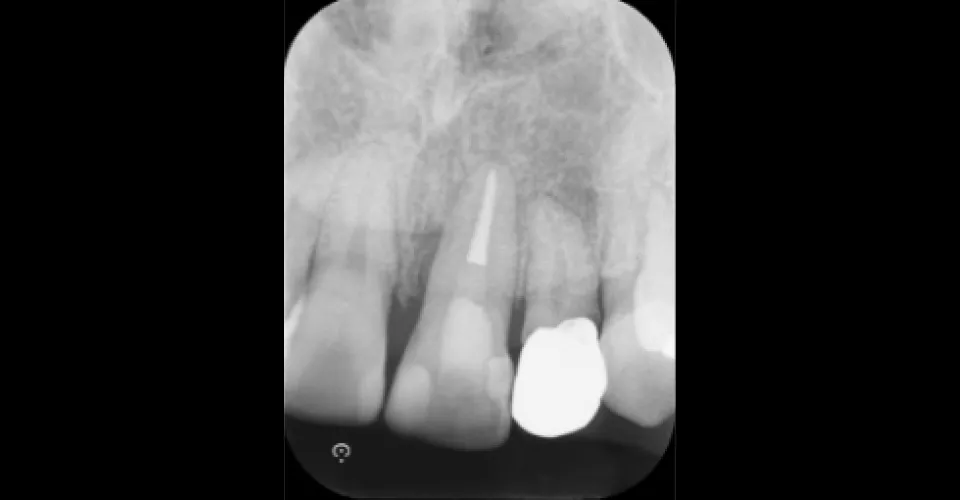

症例1

- 治療名

- 精密根管治療(前歯)

- 患者様

- 50代 男性

- 執刀医

- Dr. 松田

- 治療期間

- 1回

- 治療費

- 88000円

- リスク

- 失活による歯の色調変化、審美障害